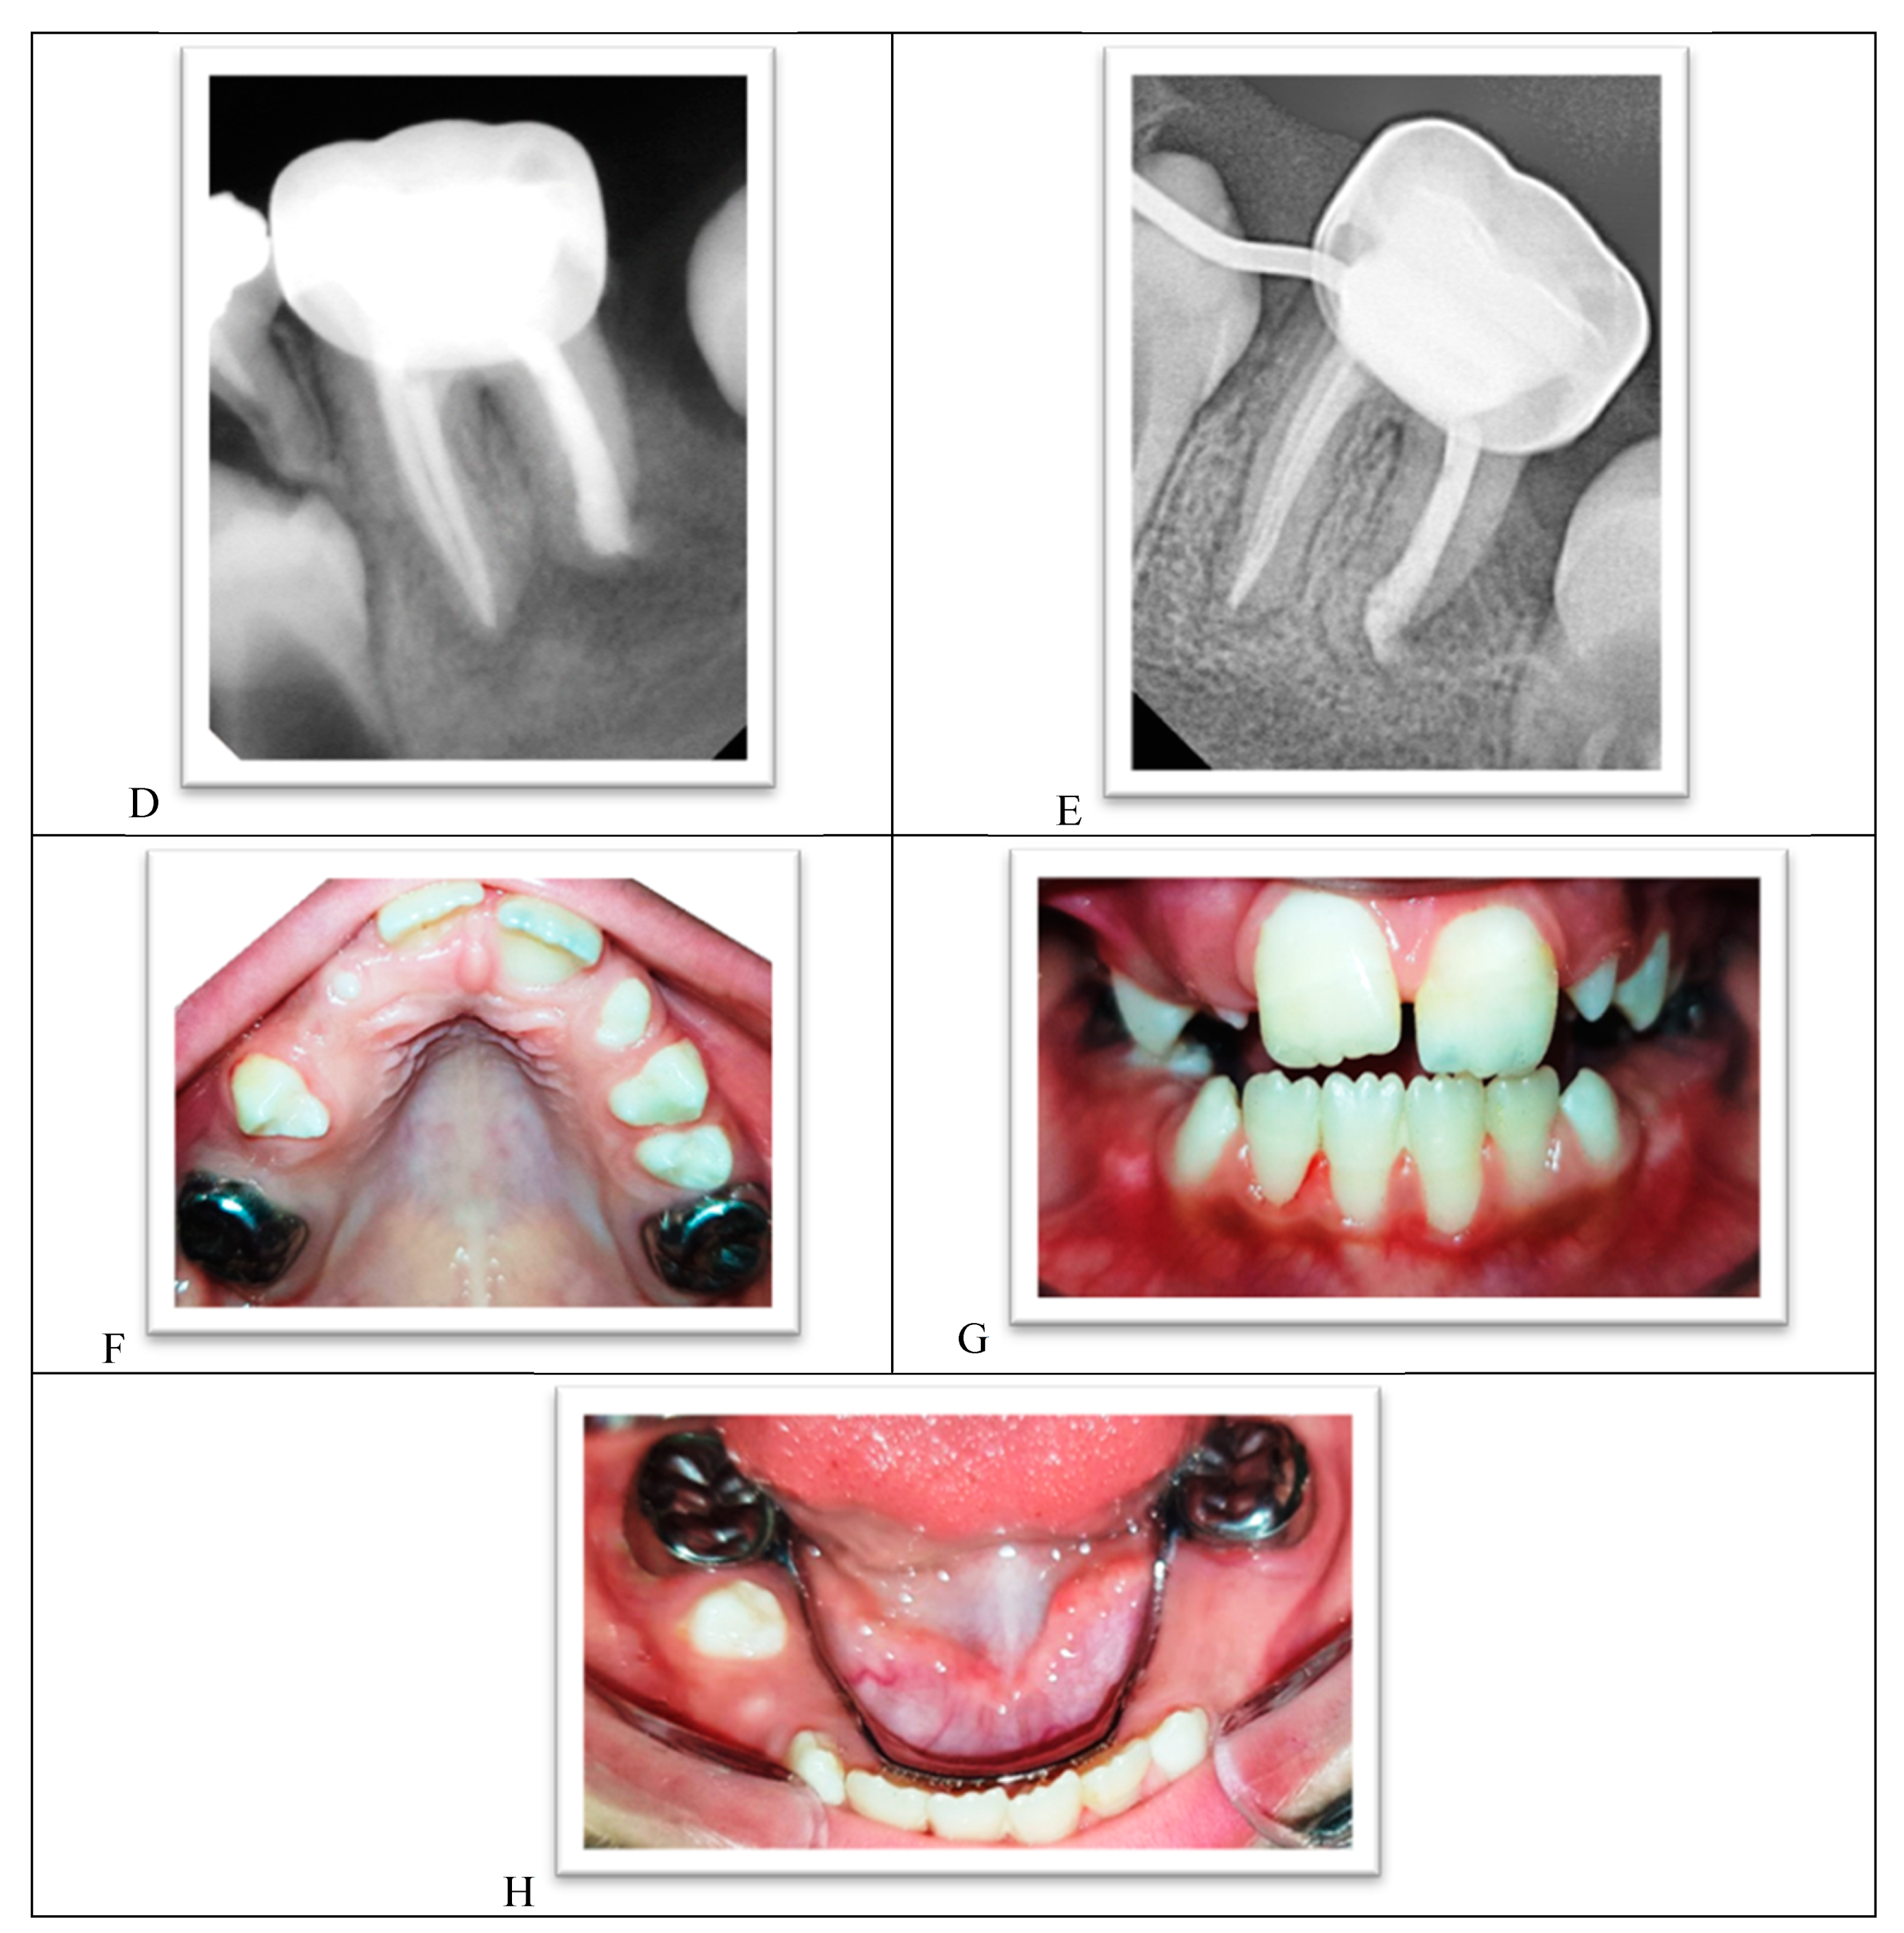

The parents reported a noticeable improvement in the child’s appetite, the disappearance of dental pain, and improved oral care and tooth brushing habits. Pit and fissure sealants were applied to the premolars as soon as they erupted, a preventive measure recommended for all high caries risk patients. The teeth were asymptomatic and functional 12 months after the operation. The size of the periapical radiolucency diminished, and full healing is expected. There was a calcified bridge under the Biodentine apical plug in the distal root. There was gradual improvement in the anterior vertical dental relationship, improvement in the lower incisor alignment, and increased transverse growth in the lower jaw (Figure 10A–H).

Figure 10.

(A) A panoramic radiograph one year after treatment. (B) The lower-right permanent molar immediately after the treatment. (C) The lower-right permanent molar one year after the treatment. Note apical healing. (D) The lower-left permanent molar immediately after the treatment. (E) The lower-left permanent molar one year after the treatment. Note apical healing. (F) The upper arch one year after the treatment. (G) Both arches in occlusion. Note the reduction in an open bite. (H) The lower arch one year after the treatment.